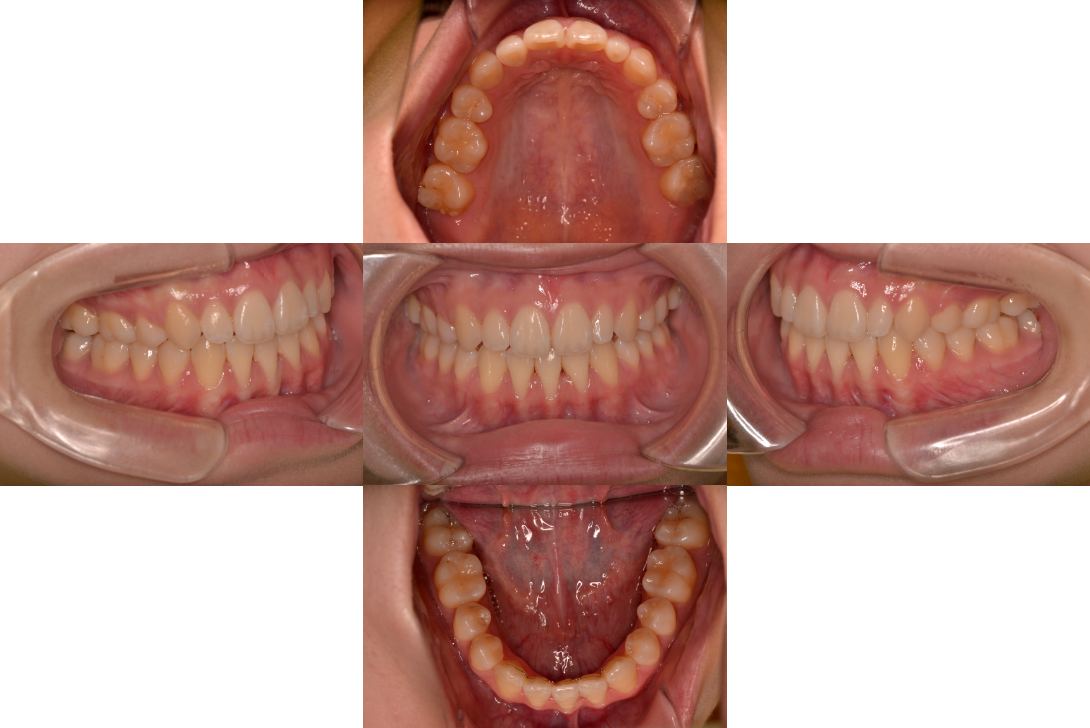

開咬(オープンバイト)を抜歯とDBSで改善した症例

※DBSとはダイレクトボンディングシステムと呼ばれており、ブラケットにワイヤーを通して歯を動かしていく矯正治療です。

患者情報

17歳女性

主訴

ガタガタの歯並びを直したい

行った治療内容

上下顎両側4番抜歯、DBS

治療のリスク

歯肉退縮、歯根吸収

治療期間

動的治療期間4年3か月 (来院がとびとびだった)

※ クリックして拡大することができます。